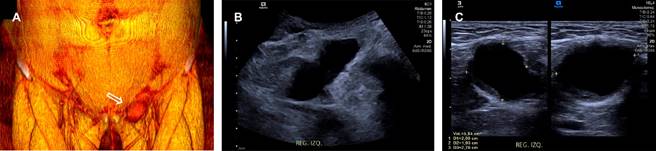

Una mujer de 45 años con antecedentes de dismenorrea e hiperpolimenorrea presentó dolor abdominal intenso y aumento de volumen en región inguinal izquierda. Los estudios de imagen revelaron una lesión hipoecoica en el ligamento redondo (Figura 1), sin aumento de vascularidad en el Doppler color y una imagen hipodensa en la tomografía (Figura 2). Se realizó una exéresis quirúrgica completa de la lesión sin complicaciones. Posteriormente, el resultado histopatológico reportó que se trataba de un foco endometriósico glandular.

Figura 1: (A) Reconstrucción 3D de tomografía computarizada, que muestra un aumento de volumen en la región inguinal izquierda (flecha hueca). Imágenes de ultrasonido en escala de grises con transductores convexo (B) y lineal (C) de la misma región, donde se observa una imagen hipoecoica de 27 × 20 × 19 mm y un volumen de 5.8 cm3, en el trayecto del ligamento redondo ipsilateral.